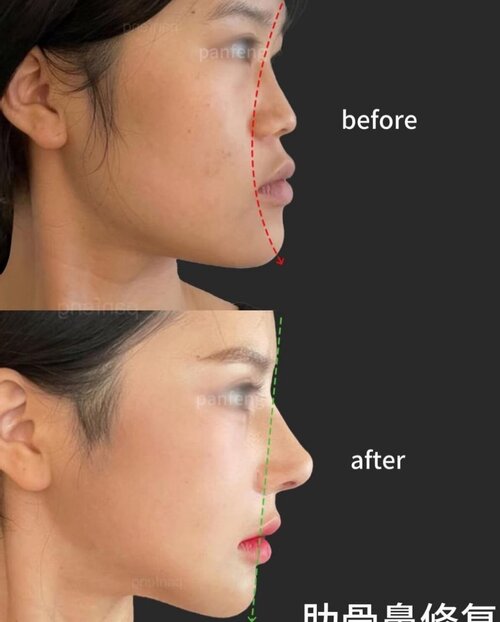

- This approach is usually paired with a projection rhinoplasty, where the surgeon grafts the dorsum, tip, and ANS. It is common in Asia and often gives great results. The extra nose projection pulls midface soft tissue forward, making the transition from the maxilla to the nose smoother whilst giving the illusion of forward growth.

The last example is especially impressive, earlier examples had grafts along the whole nose, this one used a single graft on the ANS and still pushed the nasal base forward, proof that you can fix ANS projection without touching the rest of the nose.